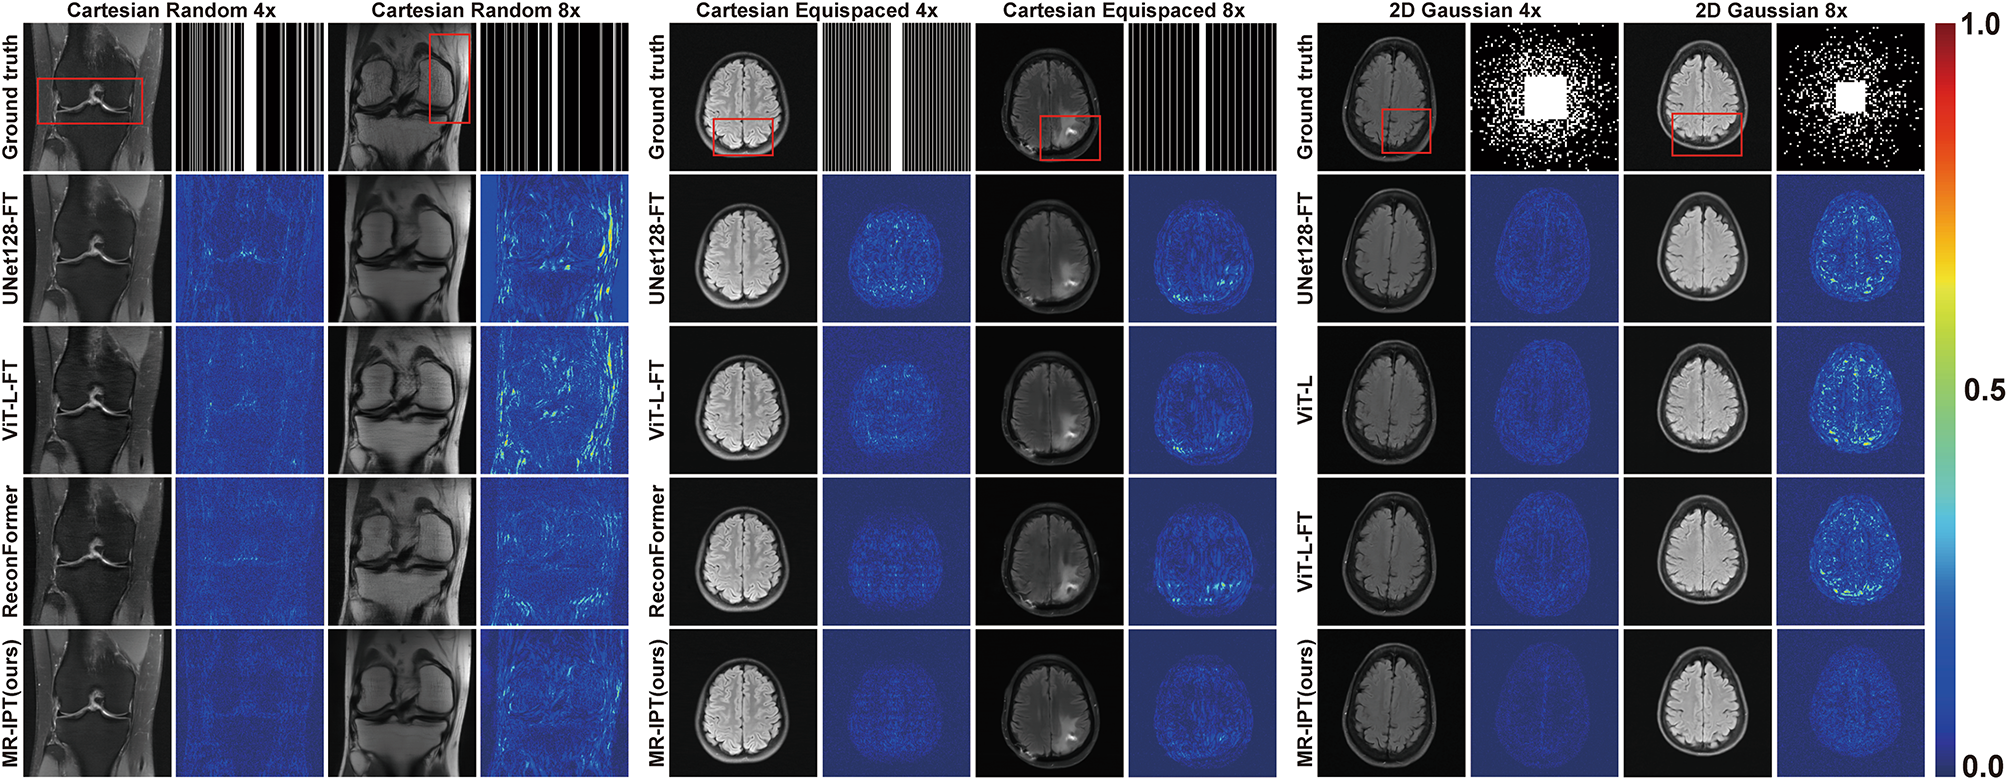

Fig. 2

From: Magnetic resonance image processing transformer for general accelerated image restoration

Restoration comparison across different models. Each column presents reconstructed images from various methods, highlighting differences in image quality and artifact suppression. The second column of each subplot shows the corresponding error maps (intensified by a factor of three for better visualization), which visualize absolute differences between the reconstructed images and the fully sampled ground truth. The red boxes highlight areas of differences among models.